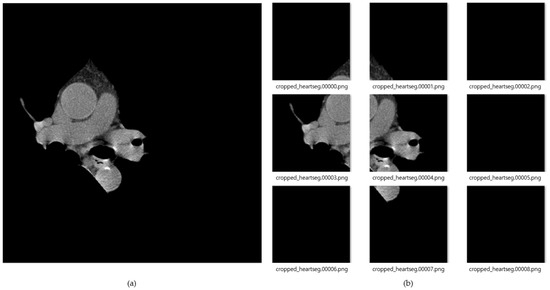

Figure 8 shows the result of images created by dividing the data into nine segments using the cardiac region segmentation data. The image data divided into nine was resized to 299 × 299 pxl size for deep-learning training. General CT images are stored as dcm file format with HU value. In this paper, we applied PNG file format with pixel values. This can be readily used for real-time labeling using a general camera, and as an assistant tool for medical doctors in the future. During data deep-learning training for this image data, there were frequent situations in which training did not proceed, due to lack of memory because of the use of many convolution layers. Therefore, we reduced the batch size to train three CNN models, and applied dropout to prevent overfitting. In the case of training accuracy and training loss, good results were obtained; but in the case of validation, splattered values occurred, due to the lack of training data. To solve this problem, the amount of data was increased by changing the angle, left, right ratio, and position values of the image through the validation generator.

Figure 8.

(a) Cardiac segmented images, and (b) cardiac cropped images created by dividing the segmented cardiac images into 9.